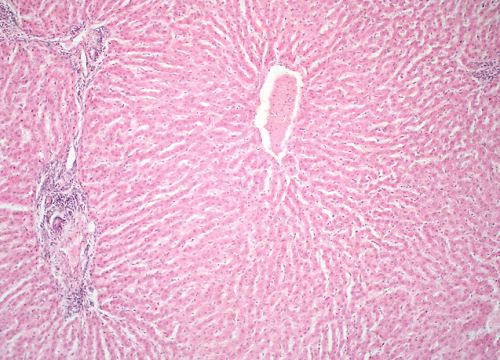

Question 17

Question

Label this image

Image:

8066b642-4ec5-4e65-99d1-e2e1e29f251b (image/png)

Answer

Liver